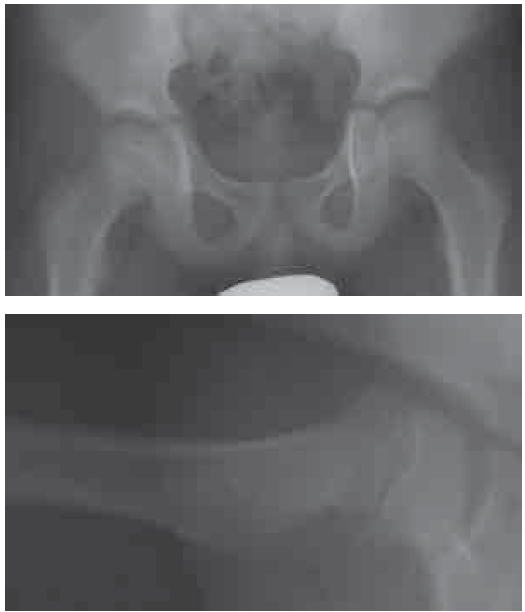

■ 問35

8歳男児、股関節痛。画像所見から正しいものを2つ選べ。

a. 安定型である

b. 可動域制限は生じない

c. 保存的療法が選択される

d. crescent signが認められる

e. 大腿骨骨端部が後方に転位している

正解:a, e

解説:大腿骨頭すべり症(SCFE)

- 安定型・後方転位が画像で確認される。